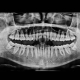

Mit Hochleistungstechnologien zu gestochen scharfen Aufnahmen – Für eine absolut präzise Diagnostik. In unserer Praxis für Implantologie und Ästhetische Gesichtschirurgie Dortmund setzen wir modernste digitale Röntgentechnologien ein, um mit Hilfe hochauflösender, dreidimensionaler Röntgenaufnahmen eine absolut präzise Diagnose stellen zu können.

Die Beurteilung der Aufnahmen erfolgt durch unsere Spezialisten. Komplizierte Fälle können dank der hochentwickelten Radiologietechnik zeitnah und schnell dokumentiert und besprochen werden. Die Strahlenbelastung bei digitaler Röntgentechnik liegt weit aus geringer als bei herkömmlichen, analogen Radiologieverfahren.